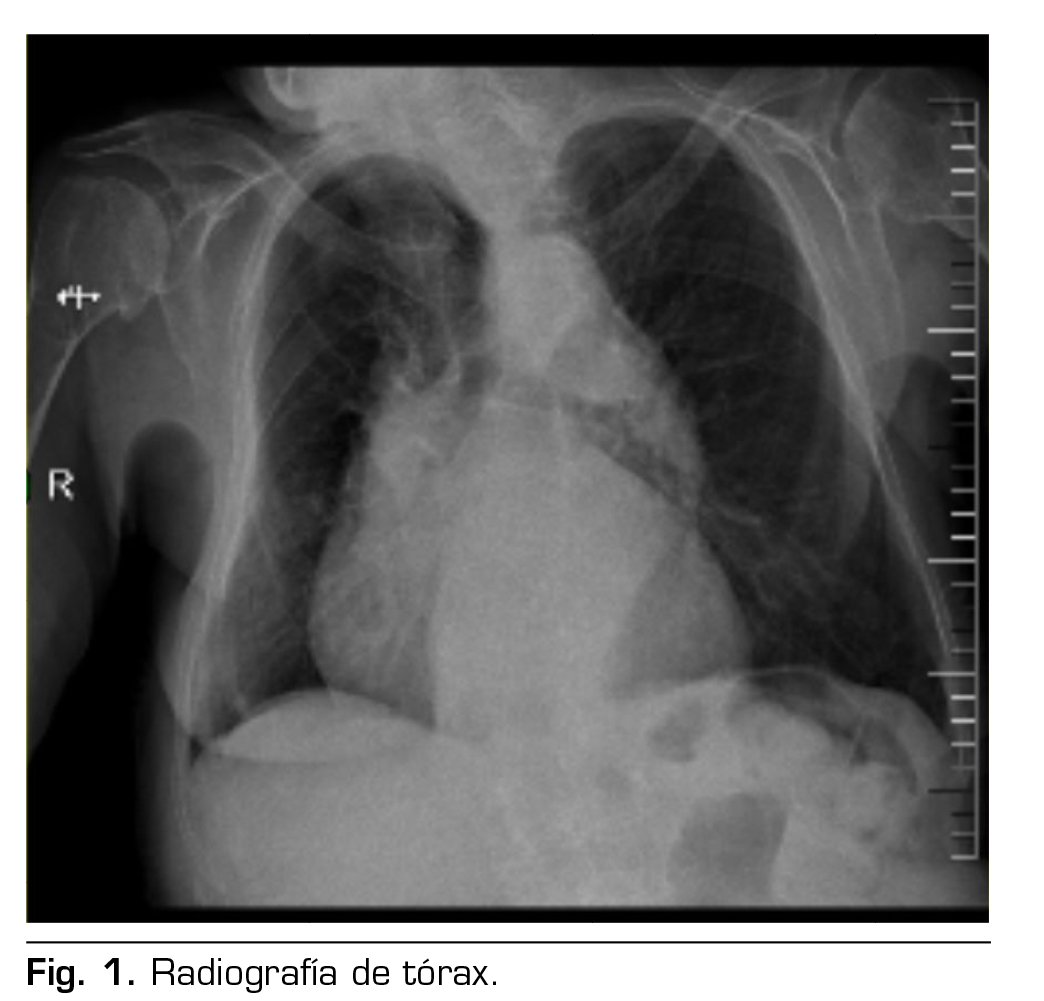

Presentación de caso: Presentamos el caso clínico de un paciente adulto mayor de 88 años ASA III, sometido a una hernioplastia inguinal electiva, bajo anestesia regional: bloqueo II/IH bajo guía ecográfica más sedación, manejo analgésico complementario con paracetamol y antinflamatorios, alta de cirugía médica ambulatoria a su domicilio y control postoperatorio sin complicaciones.

Case presentation: We present the clinical case of an 88-year-old adult patient ASA III, for elective inguinal hernioplasty, under regional anesthesia: Ilioinguinal-Iliohypogastric block under ultrasound guidance plus sedation, complementary analgesic management with paracetamol and anti-inflammatory drugs, discharge from outpatient surgery to his home and postoperative control without complications.

Figura 2